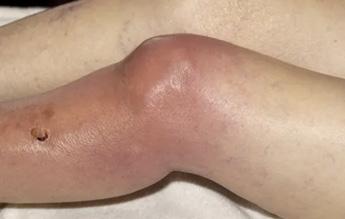

Tabla 1. Etiología Figura 1. Artritis séptica

La presentación más común es articulación caliente, roja, dolorosa y restringida

Los síntomas suelen estar presentes durante 1-2 semanas

Los síntomas sistémicos pueden incluir fiebre y malestar

La mayoría de los pacientes tienen una sola articulación afectada, aunque alrededor del 20% tienen múltiples articulaciones afectadas. La más frecuente en adultos es la rodilla y en niños la cadera. (ESSALUD 2018)